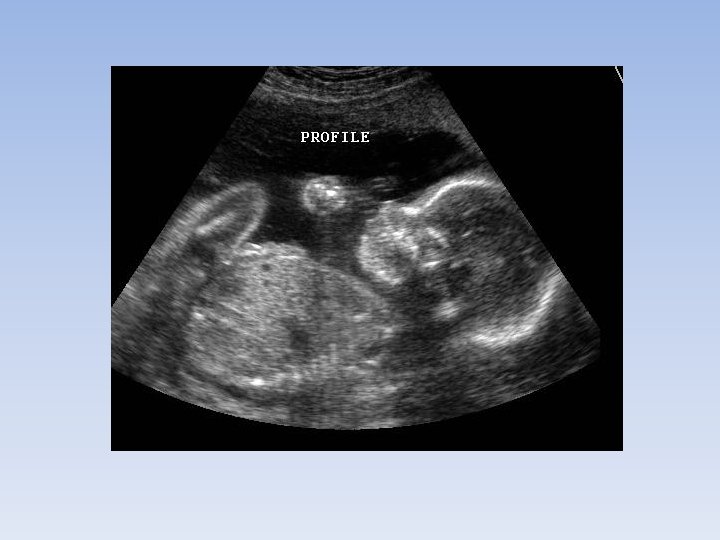

ultrasound • Use of high frequency sound waves to produce images of tissues and organs (soft tissues). • A transducer is placed on the skin and produces soundwaves that enter the body and are reflected back. • This reflection creates and image. • It is not used for bones because the sound cannot penetrated bones and not used for the intestinal tract because air bubbles can distort the image. • Ultrasounds are commonly used during pregnancy to study the developing fetus.